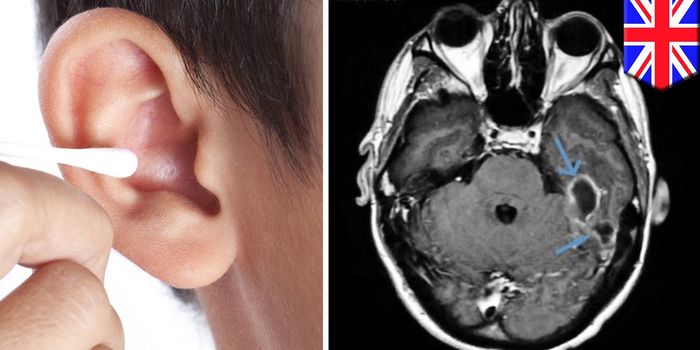

MAR 20, 2019VideosA 31-year-old British man had to go to the hospital after getting an infection in his ear that spread to the lining of h ...